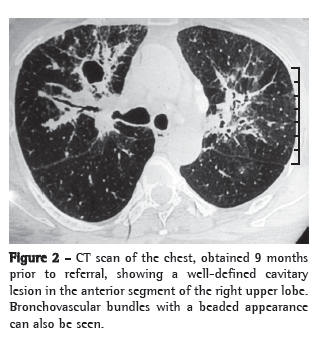

On reviewing a chest X-ray taken 9 months prior to referral, when antituberculosis therapy had been initiated, we observed diffuse, patchy opacities in both lungs, together with bilateral hilar adenopathy (Figure 1). An acinar pattern with areas of confluence was apparent in the right middle and lower fields. A CT scan of the chest, also obtained 9 months prior to referral, showed a well-defined cavitary lesion, not visible on the chest X-ray, in the anterior segment of the right upper lobe (Figure 2). In addition, we observed ground-glass opacities, accompanied by perihilar areas of consolidation and bronchovascular bundles with a beaded appearance. Bilateral hilar lymphadenopathy and asymmetric mediastinal lymphadenopathy, without caseation or rim enhancement, were also present. The cavitation seen on the CT scan probably prompted the initiation of the antituberculosis therapy. The laboratory evaluation at that time showed hemoglobin of 13.3 g/dL, with a total leukocyte count of 6,700 cells/mm3 and a normal differential leukocyte count. Although routine urine testing revealed traces of glucose, blood glucose values were within the normal range, since the patient was under treatment with oral hypoglycemic agents. The results of liver and kidney function tests, as well as the lipid profile and electrocardiographic findings, were also within normal limits. Sputum smear microscopy and culture for Mycobacterium tuberculosis and other aerobic organisms continued to yield negative results. Tuberculin testing with a 5-TU dose of PPD resulted in no induration.